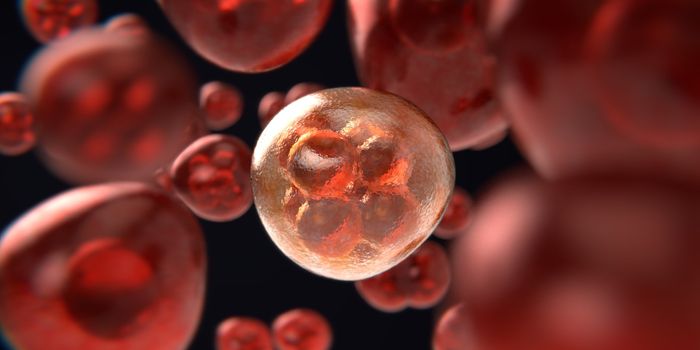

APR 17, 2024Cell & Molecular BiologyMulticellular organisms, including humans, can be incredibly complex even though they start from one fertilized cell. Th ...